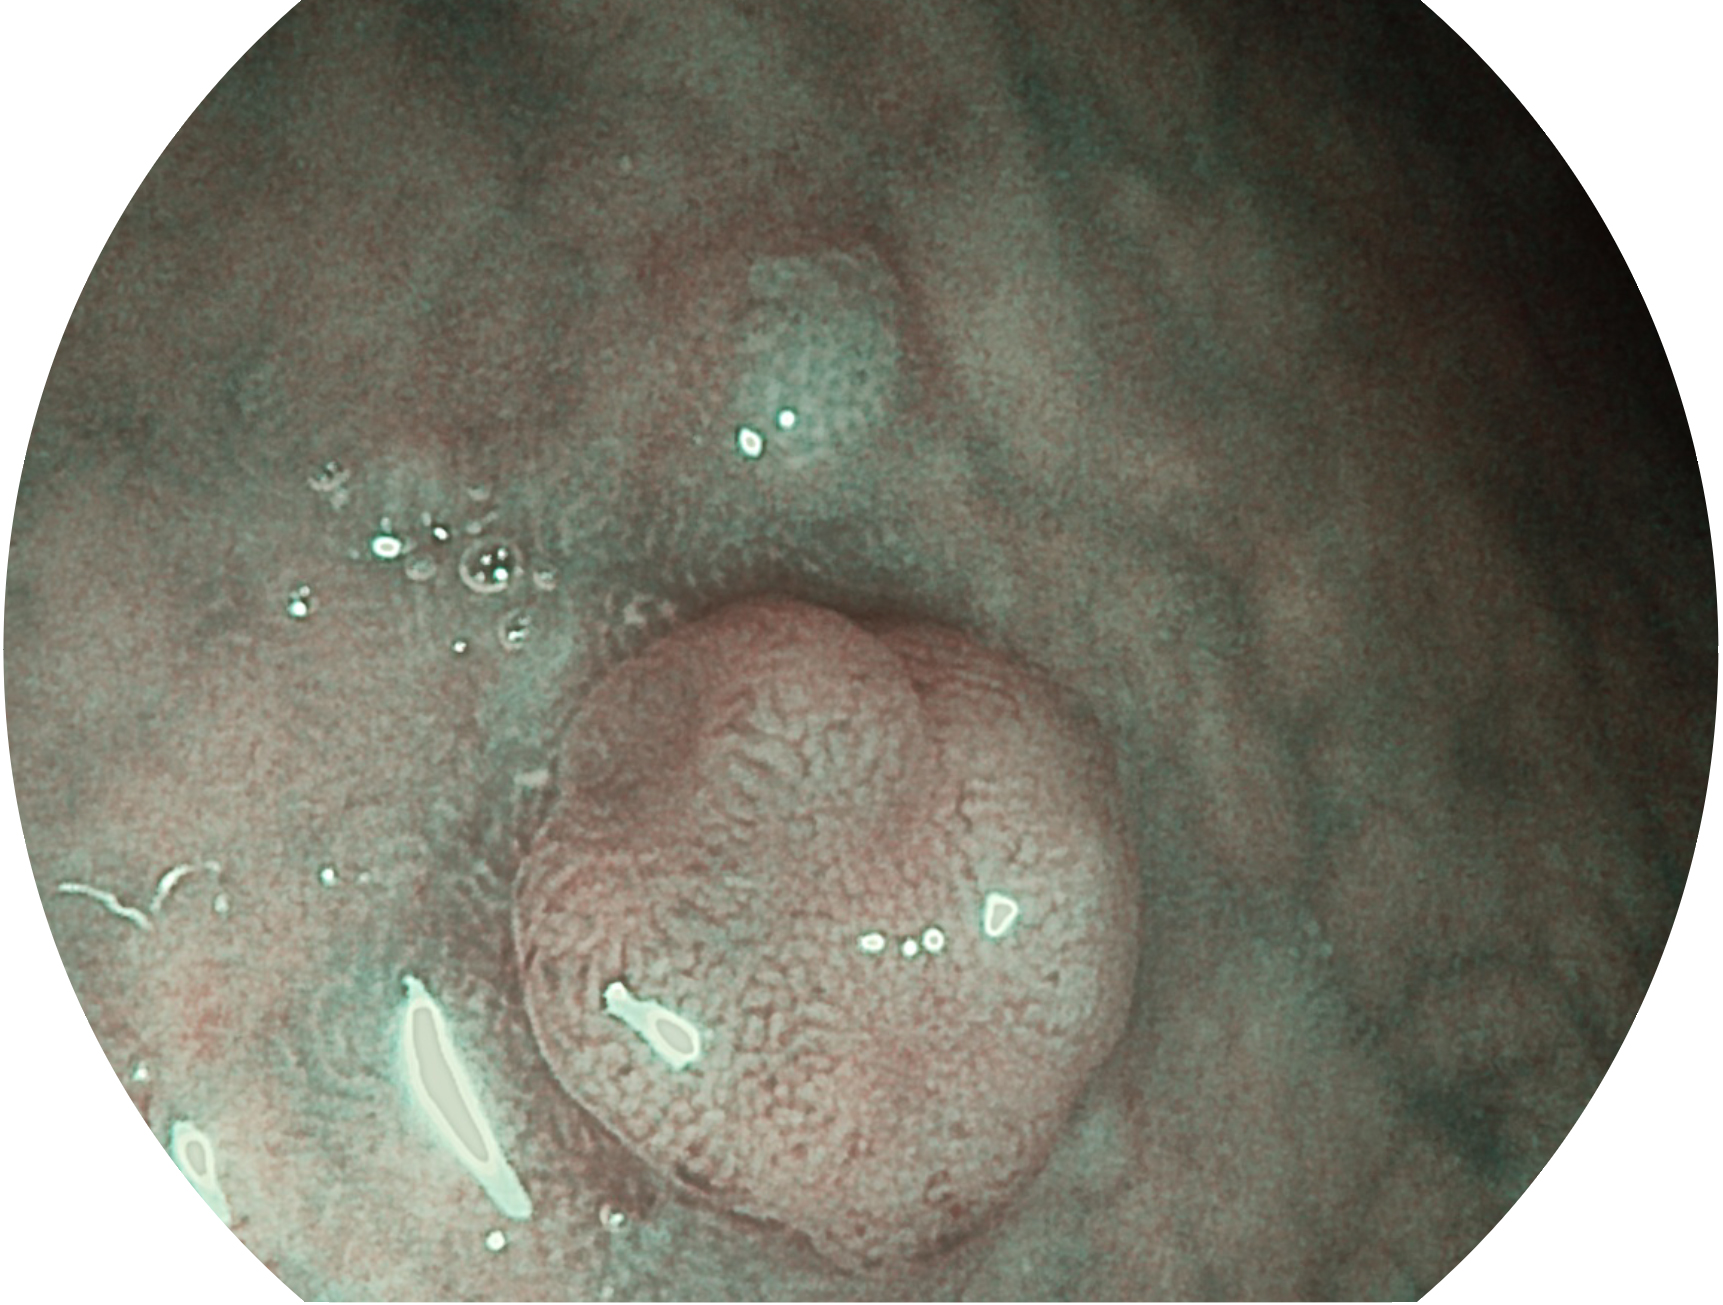

開立新開發(fā)的內(nèi)鏡染色技術(shù),主要是基于多波長LED 光源的開發(fā),VLS-55Q 四波長LED 光源是由四個(gè)不同顏色的LED光按照相應(yīng)照明模式所規(guī)定的特定發(fā)光比例進(jìn)行合束后形成,合束后形成的照明光的光譜由紅光、綠光、藍(lán)光及藍(lán)紫光這四個(gè)不同的波段范圍構(gòu)成。具有更高光譜自由度,通過光譜比例的控制,實(shí)現(xiàn)了聚譜成像技術(shù),英文全稱為“Spectral Focused Imaging, SFI”,縮寫為“SFI”和光電復(fù)合染色成像技術(shù),英文全稱為“Versatile Intelligent Staining Technology, VIST”,縮寫為“VIST”。